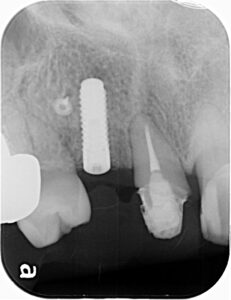

本日のインプラント症例は右上側切歯(2番目)です。レントゲンではわかりにくいですが破折していました。

半年後、骨が確認できたのでインプラントを埋入しました。